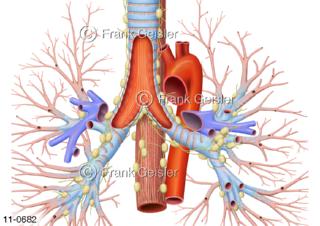

11-0682 Luftröhre Trachea mit Bronchien, Organe mit Lymphgefäße Lymphknoten